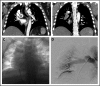

Patients who present with severe manifestations of acute venous thromboembolism (VTE) are at higher risk for premature death and long-term disability. In recent years, catheter-based interventional procedures have shown strong potential to improve clinical outcomes in selected VTE patients. However, physicians continue to be routinely faced with challenging decisions that pertain to the utilization of these risky and costly treatment strategies, and there is a relative paucity of published clinical trials with sufficient rigor and directness to inform clinical practice. In this article, using 3 distinct clinical scenario presentations, we draw from the available published literature describing the natural history, pathophysiology, treatments, and outcomes of VTE to illustrate the key factors that should influence clinical decision making for patients with severe manifestations of deep vein thrombosis and pulmonary embolism. The results of a recently completed pivotal multicenter randomized trial are also discussed.